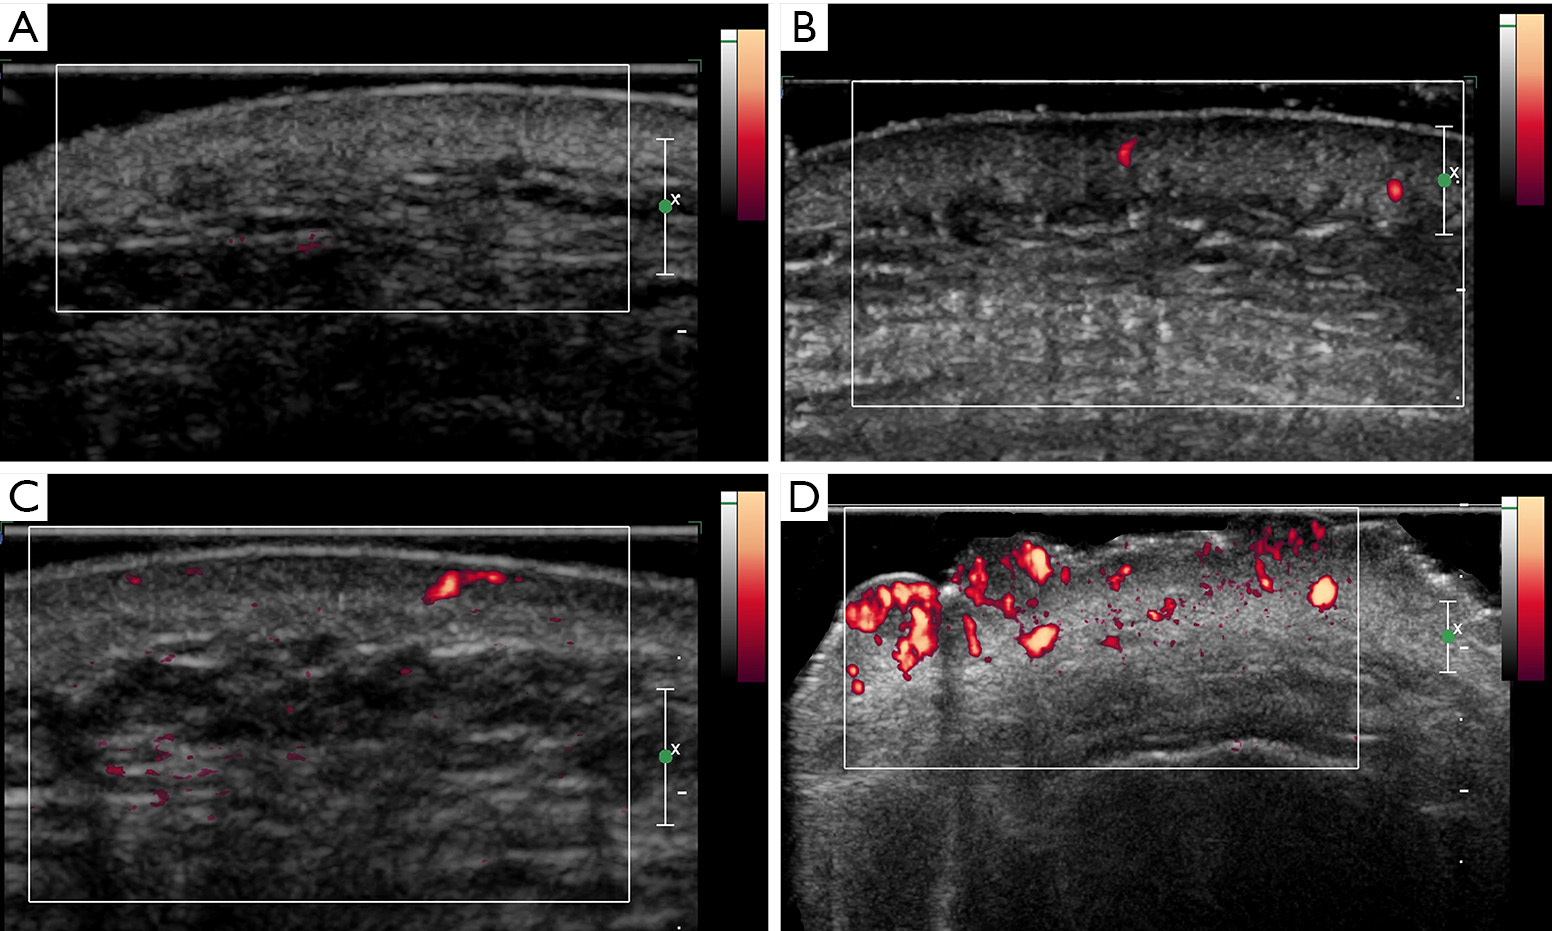

Clinical images with corresponding high frequency ultrasound and High Frequency Ultrasound Clinical We provide a brief history of its introduction to. in this review, we discuss how hfus fits into the landscape of skin imaging. in this paper, we present the role and potential clinical applications of uhfus in musculoskeletal imaging based. High Frequency Ultrasound Clinical.